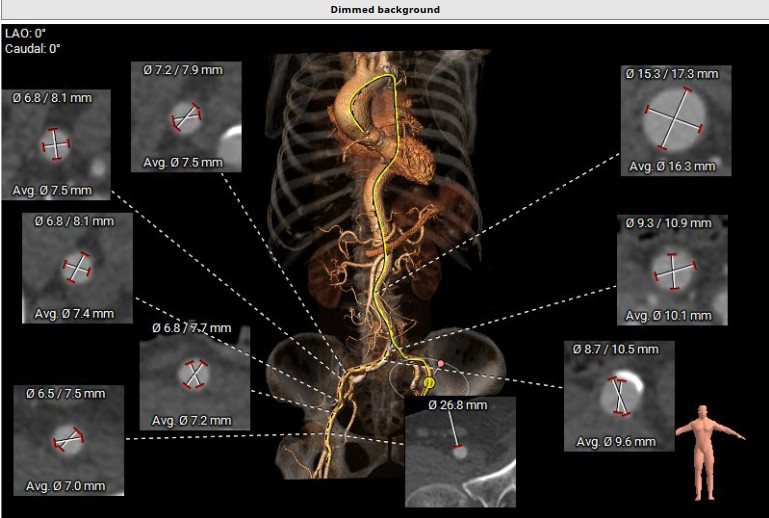

患者术前CT分析:主动脉瓣为三叶式,瓣叶增厚;主动脉弓角度偏小。

外周血管